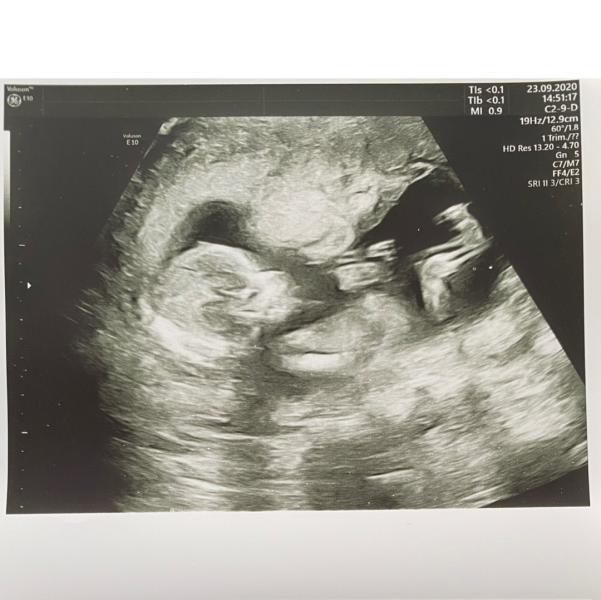

Первый скрининг

Первый скрининг у меня был 23 сентября. Если считать от первого дня последнего цикла, то мой срок составлял ровно 14 недель.